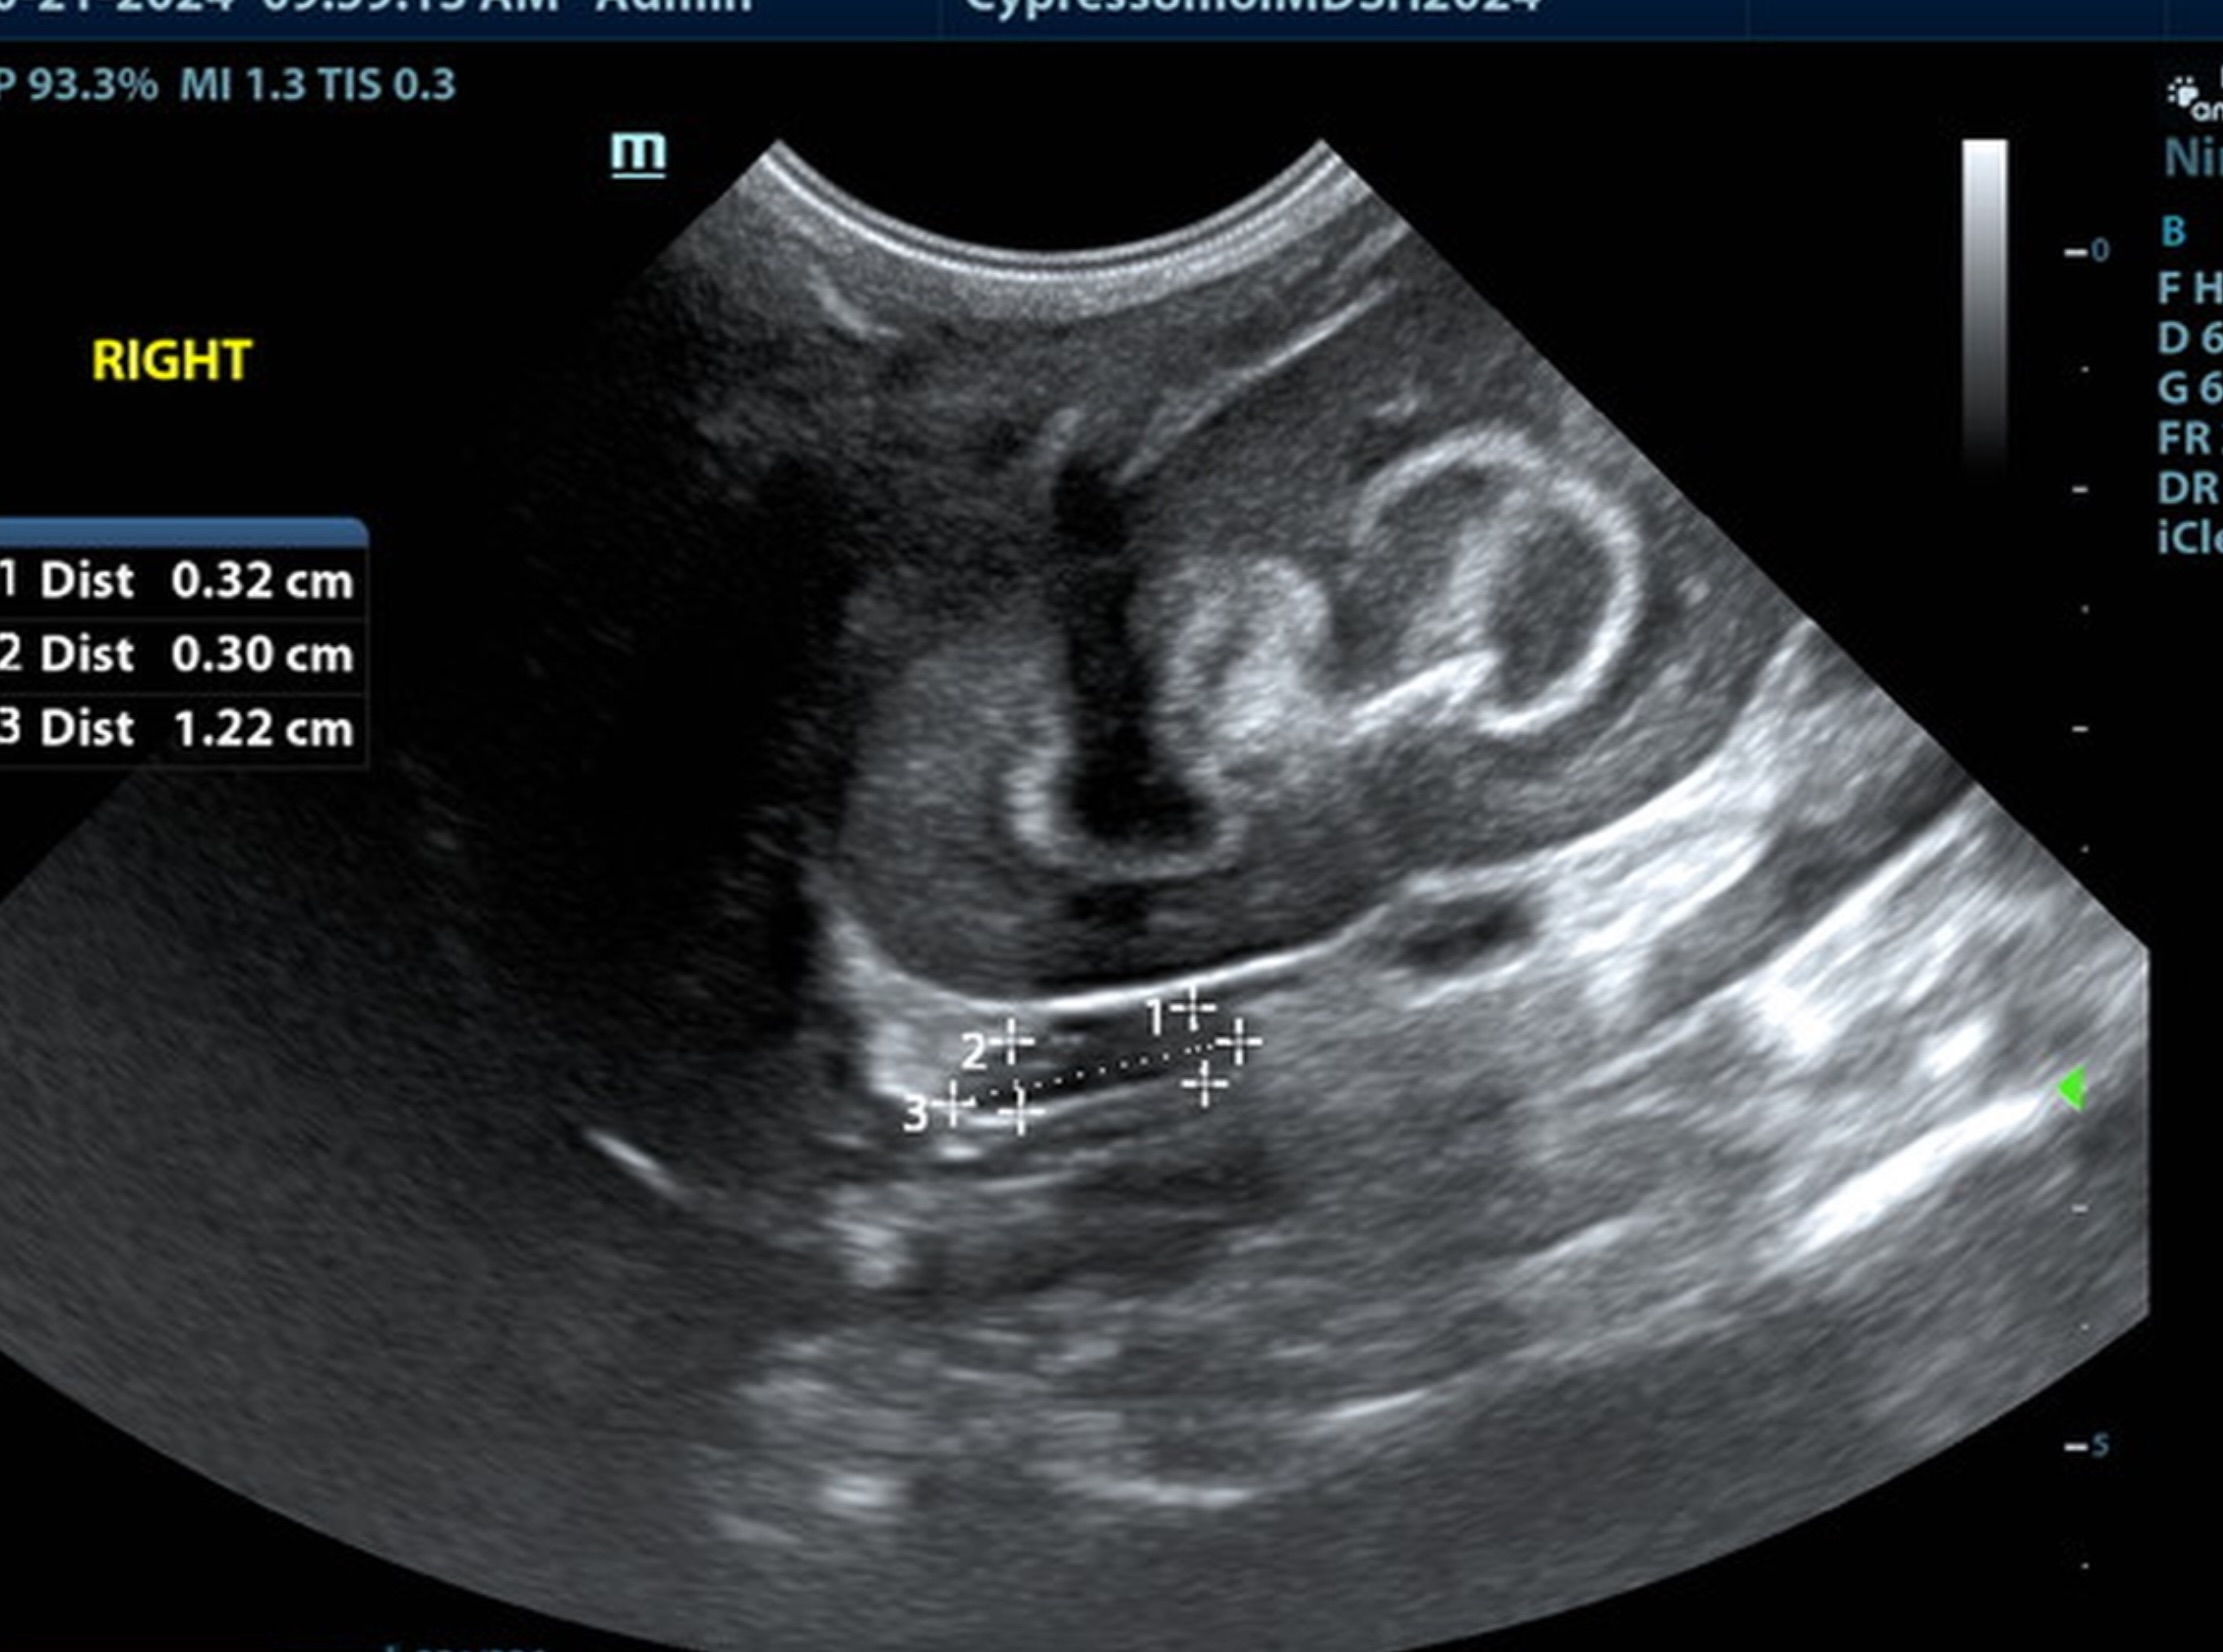

The liver was subnormal in size, yet the portal vein and vena cava ratio was 1:1. The portal veins were subnormal in size and measured 0.34 cm. The vena cava was enlarged and measured 0.34 cm. The vena cava was enlarged and measured 0.72 cm, aorta measured 0.4 cm. The branching of the portal vein appeared to be normal and of adequate volume. The portal vein and vena cava measured 0.5 cm each in the extrahepatic space. The splenic vein entry into the portal vein and gastroduodenal vein entry into the portal vein appear to be normal. There was one turbulent vessel in the region of the central branch of the portal vein, which may represent an intrahepatic shunt, but this could not be confirmed. The width of the shunt is approximately 0.76 cm. This is in position of central divisional shunt; however, right divisional origin cannot be completely ruled out. The gallbladder presented acceptably thin walls with primarily anechoic content. The cystic and common bile ducts were normal.